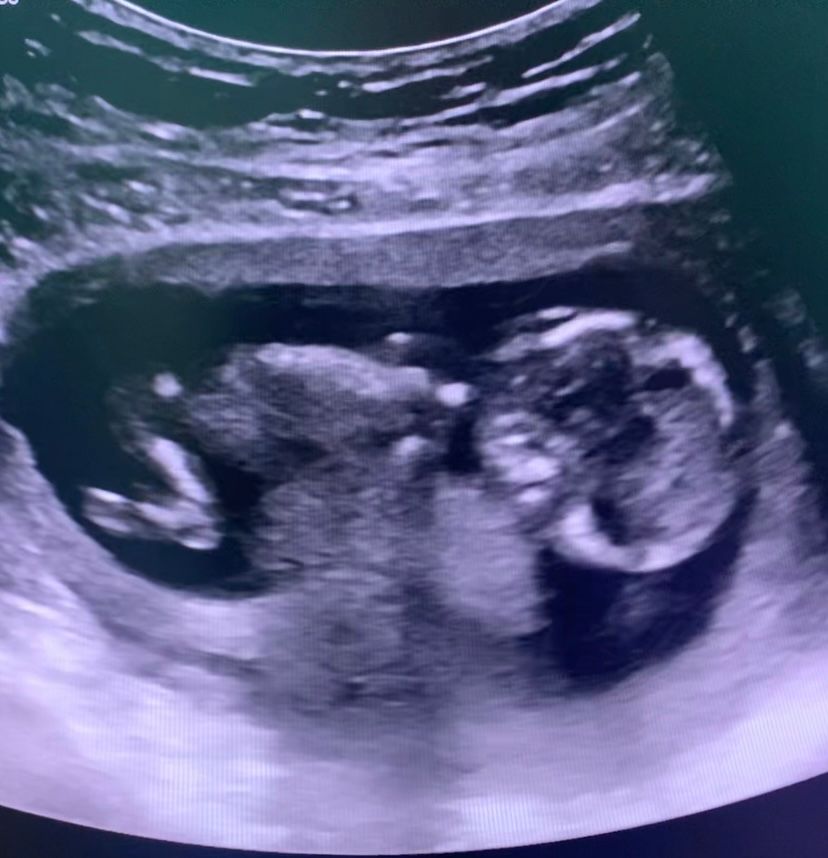

Эва, еще может быть узистка не айс поэтому не видит) не знаю почему но на последнем фото мне кажется я отчетливо вижу и носик и носовую кость

Солнце, вот и я кажется все вижу,может конечно потому,что хочу но уже хз,возможно она долго меня крутила и малыш говорит как-то неудобно лежит

У вас есть носовая косточка, я ее вижу. Уверена, у вас все хорошо

Family, 🙏вот и мне кажется я ее вижу,спасибо ❤️